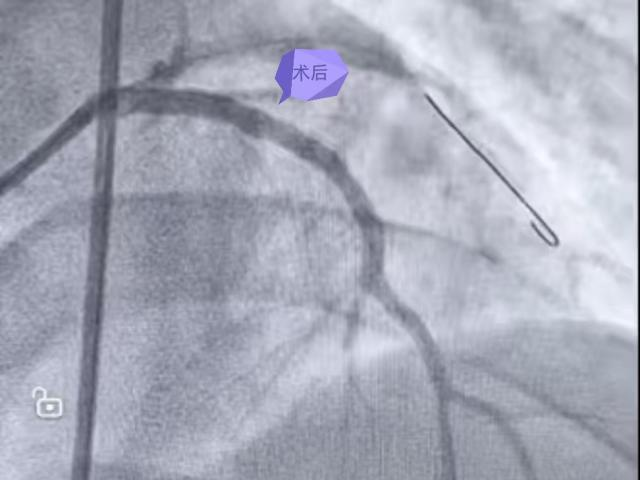

胸痛突袭,生命告急 “心”危机终化险为夷 ❤️❤️❤️ 9月的一天,36岁的朱先生突然感到胸部持续剧痛。当地卫生院医生第一时间完成心电图检查,判断可能是“急性心肌梗死”,并立即启动与贵州航天医院胸痛中心的联动。 在转诊救护车上,急救人员已遵照胸痛中心的指导为朱先生用上了必要的药物。可就在车辆抵达贵州航天医院急诊科的那一刻,险情骤然升级——朱先生出现了呼吸心跳骤停、反复室颤!急诊科团队立即就地展开抢救,通过持续心肺复苏、紧急气管插管、呼吸机辅助通气及十余次电除颤等紧张有序的处置,朱先生终于恢复了自主心跳,待其生命体征趋于平稳后,便被火速转运至导管室进行后续救治。 在心血管内科、导管室、麻醉科的通力配合下,冠状动脉造影很快找到了“元凶”——心脏的一根重要血管(前降支)被完全堵死。与家人充分沟通后,团队迅速为朱先生开通了堵塞的血管,并植入一枚支架。从入院到血管开通,这场关键手术仅用了45分钟。术后,经过多学科团队两周的精心照护,朱先生恢复良好,现已顺利出院。 这场“接力赛”为何能成功? 1.基层“哨兵” 乡镇医生准确识别、快速转诊,抢下最初宝贵时间。 2.120“生命快车” 途中持续监护与用药,搭建起移动的生命桥梁。 3.医院“专家团队” 多科室紧密协作,应对突发状况,以精湛技术打通生命通道。 【健康小课堂】 ▶如何识别心梗信号? 典型表现: 突发性、压榨性的胸骨后疼痛,可能放射到左肩、背部、下颌或手臂,常伴大汗、恶心、濒死感。 不典型表现(尤其需警惕!): 对于部分人群,可能只表现为莫名的乏力、头晕、气短、恶心呕吐,甚至只是牙痛、喉咙发紧或上腹痛。 ▶记住两个“120”,关键时候能救命! 一旦怀疑是心梗,立即拨打120急救电话!不要自行驾车或打车去医院,以免途中发生意外,争取在120分钟内开通堵塞的血管。 ▶防大于治,别拿生命开玩笑! 预防永远是第一位的。高血压、高血脂、糖尿病等慢性疾病,以及吸烟、熬夜、缺乏运动、饮食不节等不健康生活习惯,都会默默损害血管健康。这就像一条原本光滑的管道,长期受损后会变得粗糙,杂质(如血脂)就容易沉积,形成“水垢”(动脉粥样斑块)。一旦“水垢”破裂,身体就会在破口处快速“打补丁”(形成血栓),这个“补丁”若完全堵死血管,心肌梗死就发生了。 时间就是心肌,时间就是生命。关注心血管健康,从识别信号、及时求助和改善生活习惯开始。 贵州航天医院 心血管内科专家简介 沈万贵 心内科党支部书记、主任,副主任医师 临床擅长:从事临床工作约33年,对冠心病,高血压病,各种心肌病等疾病的诊治以及内科疑难杂症疾病的诊疗具有丰富诊疗经验,累计实施冠心病、外周血管等疾病的介入手术诊疗过万例。擅长于冠脉复杂病变的介入手术治疗、肾动脉狭窄介入手术、下肢深静脉血栓的介入手术治疗。 贵州省医学会心血管病分会常务委员、贵州省心脏病康复医学会常务委员,遵义市医学会心血管病分会副主任委员,西南高血压病管理委员会常务理事,贵州省冠心病组委员;发表学术论文20余篇。 张羽坤 中共党员,心血管内科副主任,主任医师,硕士研究生 临床擅长:具备心血管疾病心律失常介入(导管消融及植入器械)国家级手术资质,参与各类心脏介入手术6000余例。以第一作者在国内核心期刊发表医学论文10余篇,主持市级科研项目1项。 曾先后前往贵州省人民医院、国家心脏中心北京阜外心血管病医院学习深造(2017年11月至2018年11月参加第二期黔医人才计划并获得优秀学员称号),2022年获得贵州省“第二届最美劳动者”称号。 中国医疗保健国际交流促进会心律与心电分会第三届委员,中国老年医学学会心血管病分会第二届委员会基层委员,贵州省心电生理与起搏分会委员,贵州省中西医结合学会心血管专业委员会委员,遵义医学会心血管病学分会常委,遵义市医学会(第六届)理事会理事,遵义市健康科普专家;是遵义医科大学科技学院及遵义医药高等专科学校兼职教师。 李树刚 中共党员,心血管内科主任医师 临床擅长:具备冠心病介入手术治疗资质,对心内科各种常见病、多发病及急性冠脉综合征疾病具有丰富的临床诊治经验,完成各项冠心病介入治疗6000余台。 毕业于遵义医学院临床医学专业,以第一作者在国内核心期刊发表医学论文数篇,主持并结题市级科研项目1项;遵义市医学会心血管病分会委员,遵义市健康科普专家成员。 刘忠凤 中共党员,心血管内科副主任医师 临床擅长:对结构性心脏病超声心动图的判读及解析、结构性心脏病的诊疗有丰富的临床诊疗经验;擅长心血管常见多发病及难治性心衰的诊治、恶性心律失常的抢救。 遵义市医学会心血管病分会委员,遵义市医学会内分泌暨糖尿病分会委员,遵义市医学会骨质疏松暨骨矿盐疾病学分会委员;曾前往贵州省人民医院超声心动图室、四川大学华西医院超声科进修学习超声图;发表省级期刊数篇,参与结构性心脏病术中超声指导。 李茂春 心血管内科副主任医师 临床擅长:1995年毕业于遵义医学院临床医学系,从事临床工作28年,熟练掌握高血压、冠心病等心血管疾病的诊治及危急重症患者的救治,擅长糖尿病、甲状腺功能亢进、代谢综合征等内分泌代谢性疾病的诊治,在多年的临床工作中对内分泌代谢疾病、心血管疾病的诊治中积累了丰富临床的经验。 贵州省医学会内分泌暨糖尿病学分会第七届委员会甲状腺学组组员,遵义市内分泌暨糖尿病学分会第一届委员会常务委员,贵州省康复医学会骨内科专业委员会遵义地区分会常务委员。多年来在省内外期刊发表论文数十篇。 胡兴丽 心血管内科副主任医师 临床擅长:对心血管及内分泌相关常见疾病的诊治及抢救工作具有丰富的临床经验,擅长心血管及心律失常的介入手术。 2009年毕业于遵义医学院临床医学专业,临床工作10余年,有外出进修 CCU 学习经历,发表论文数篇。云贵川高血压联盟委员。 杨 菊 中共党员,心血管内科副主任医师,硕士研究生 临床擅长:具备心血管疾病冠脉介入手术资质,参与各类冠心病介入手术3000余例。 遵义市医学会心血管病分会委员,多次获得“优秀党员”、“优秀帮扶对象”、“优秀带教老师”等荣誉称号,遵义医药高等专科学校及遵义医科大学科技学院兼职教师;以第一作者在国内核心期刊发表医学论文数篇,主持并结题市级科研项目1项。 张 禹 心血管内科副主任医师 临床擅长:熟练掌握冠心病、心律失常、高血压、心力衰竭、风湿性心脏病、扩心病等心血管疾病诊治,以及急、危、重症病人的救治。 2017年在重庆第三军医大学新桥医院心内科进修学习,2018年贵州省人民医院进修心律失常介入治疗,取得心血管疾病心律失常介入(导管消融)国家级手术资质,参与冠脉介入、射频消融、起搏器置入等心内科介入手术4000余例;是遵义市医学会心血管病分会委员。 贵州航天医院 心血管内科简介 基本情况 贵州航天医院心血管内科编制床位60张,配置了29台24小时动态心电图、110台24小时动态血压、心脏除颤仪、监护仪、输液泵、微量注射液,同步12导联、18导联心电图机、临时心脏起搏器、床旁血糖仪、主动脉内球囊反搏、食道超声、血管内超声诊断仪及DSA心血管诊疗等。 学科、专科建设 近年来成功获批胸痛中心、房颤中心、儿童先天性心脏病定点救治单位授牌;是遵义市临床重点专科、远程心电示范中心、高血压慢病管理示范中心。 科室诊疗范围 开展了急诊冠脉介入诊疗,冠脉复杂病变介入术、冠状动脉斑块旋磨术、心脏再同步治疗起搏器植入术、心脏再同步治疗除颤器植入术、射频消融术【心房颤动(导管消融、冷冻消融)、心房扑动、房性心动过速、室性心动过速、室性早搏】、结构性心脏病介入治疗【房间隔缺损(卵圆孔未闭)封堵术、室间隔缺损封堵术、动脉导管未闭封堵术、冠状动脉瘘封堵术、左心耳封堵术等】、临时起搏器植入术、常规永久起搏器植入术(双腔、单腔)、下肢动静脉造影术、下腔静脉滤器植入及取出术、自主肾上腺静脉采血、颈动脉支架植入术、外周动脉支架植入术、肾动脉支架植入术等,积极开展冠脉内超声检查、FFR、OCT、心脏射频三维手术、房颤一站式治疗(房颤射频消融术+左心耳封堵术)、主动脉瓣介入术等,并邀请院外专家指导成功开展腹主动脉支架植入术。